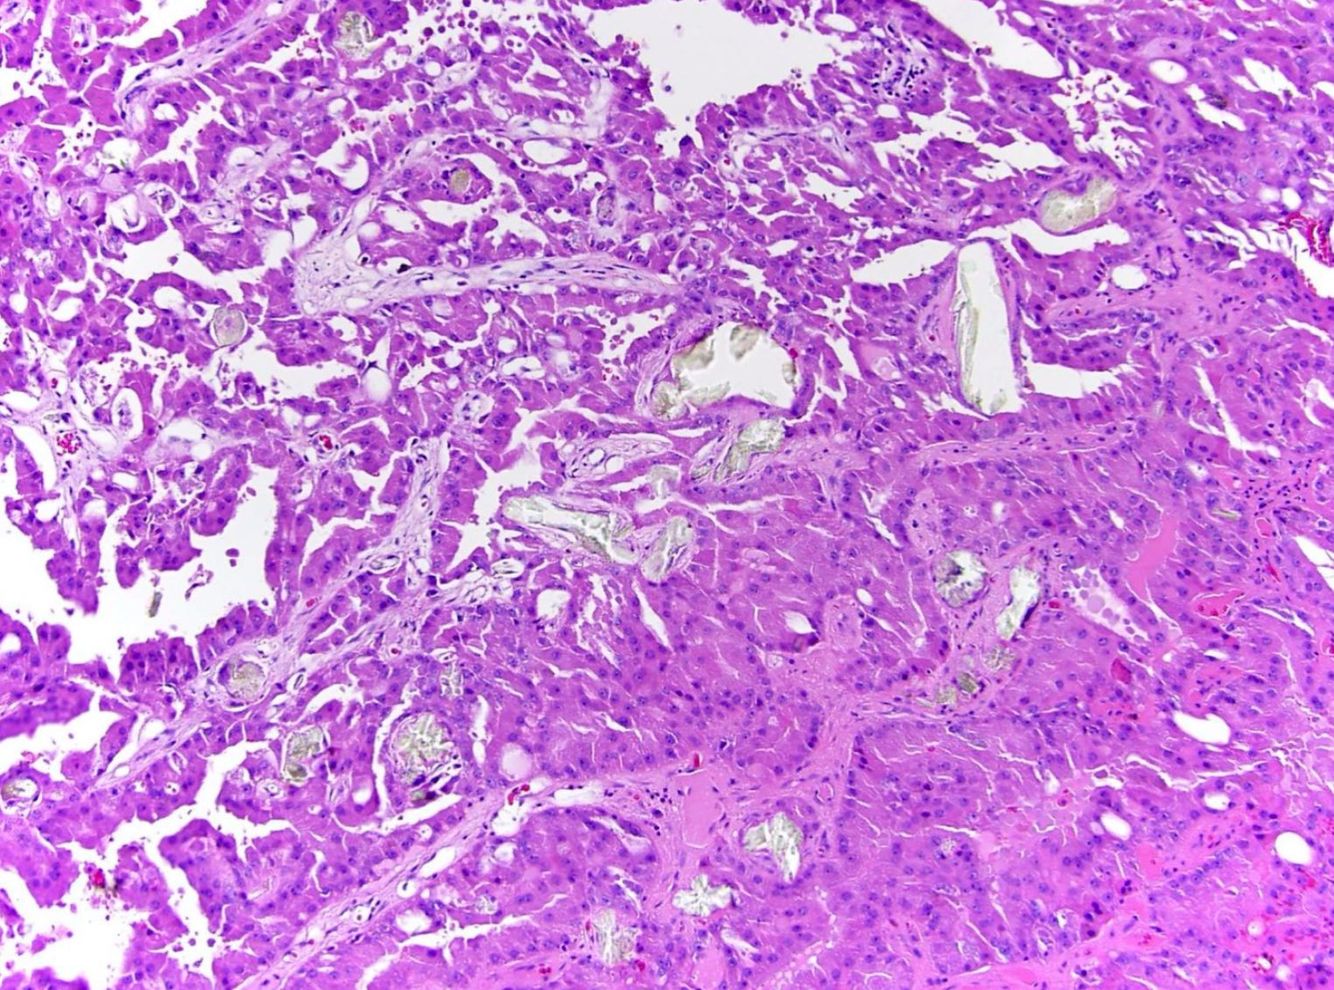

Acquired cystic kidney disease-associated renal cell carcinoma

Found in end-stage kidneys. An unmistakable grungy mix of oncocytic cells and bubbly, microcystic architecture with hemorrhage, necrosis, and oxalate crystals.

The abundant oxalate crystals are a dead giveaway, if nothing else clues you in.